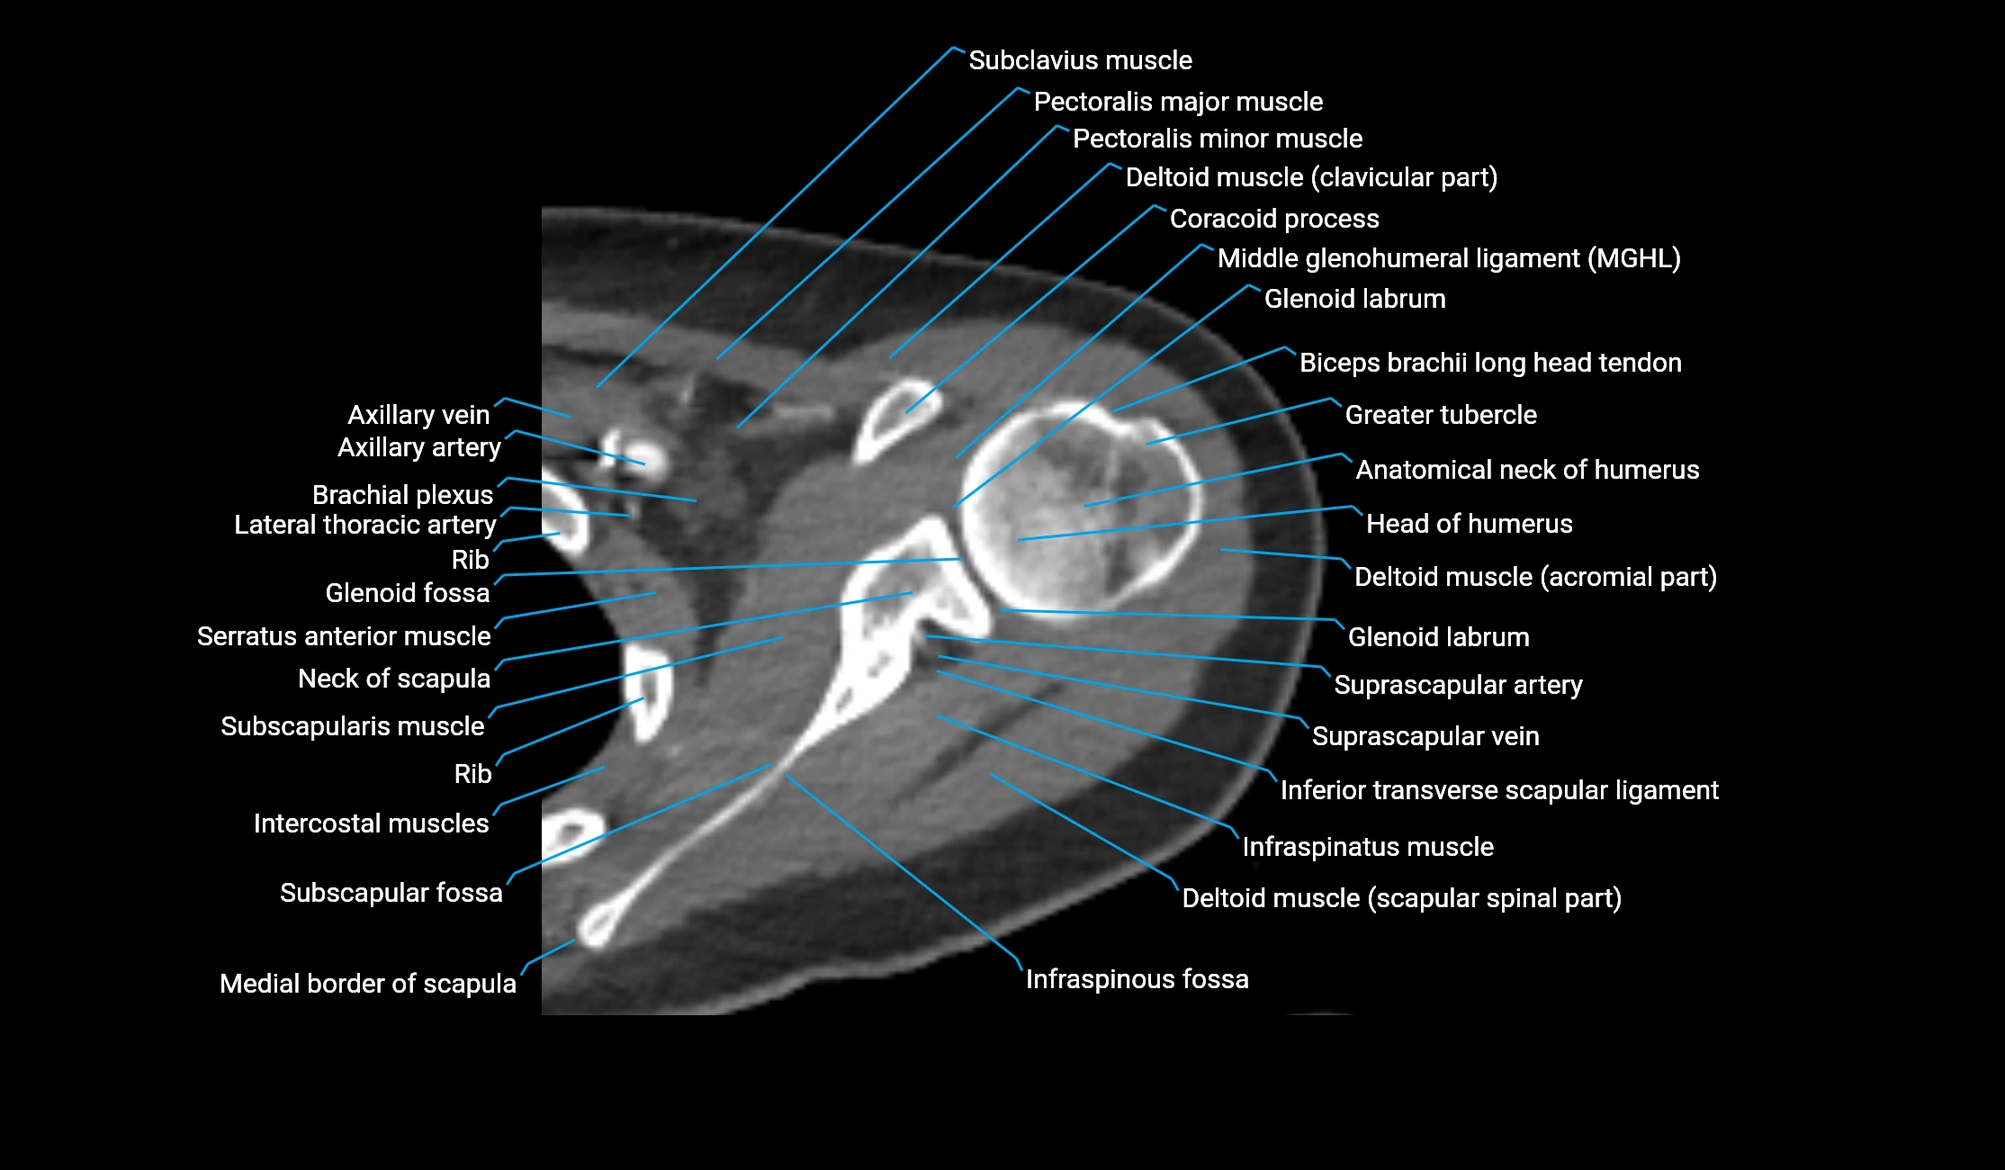

- Anatomical neck of humerus

- Brachial plexus

- Coracoid process of scapula

- Glenohumeral joint capsule

- Glenohumeral ligaments

- Glenoid fossa

- Glenoid labrum

- Greater tubercle of humerus

- Head of humerus

- Inferior transverse scapular ligament

- Infraspinatus muscle

- Infraspinous fossa

- Middle glenohumeral ligament

- Pectoralis major muscle

- Pectoralis minor muscle

- Subclavius muscle

- Subscapular fossa

- Subscapularis muscle